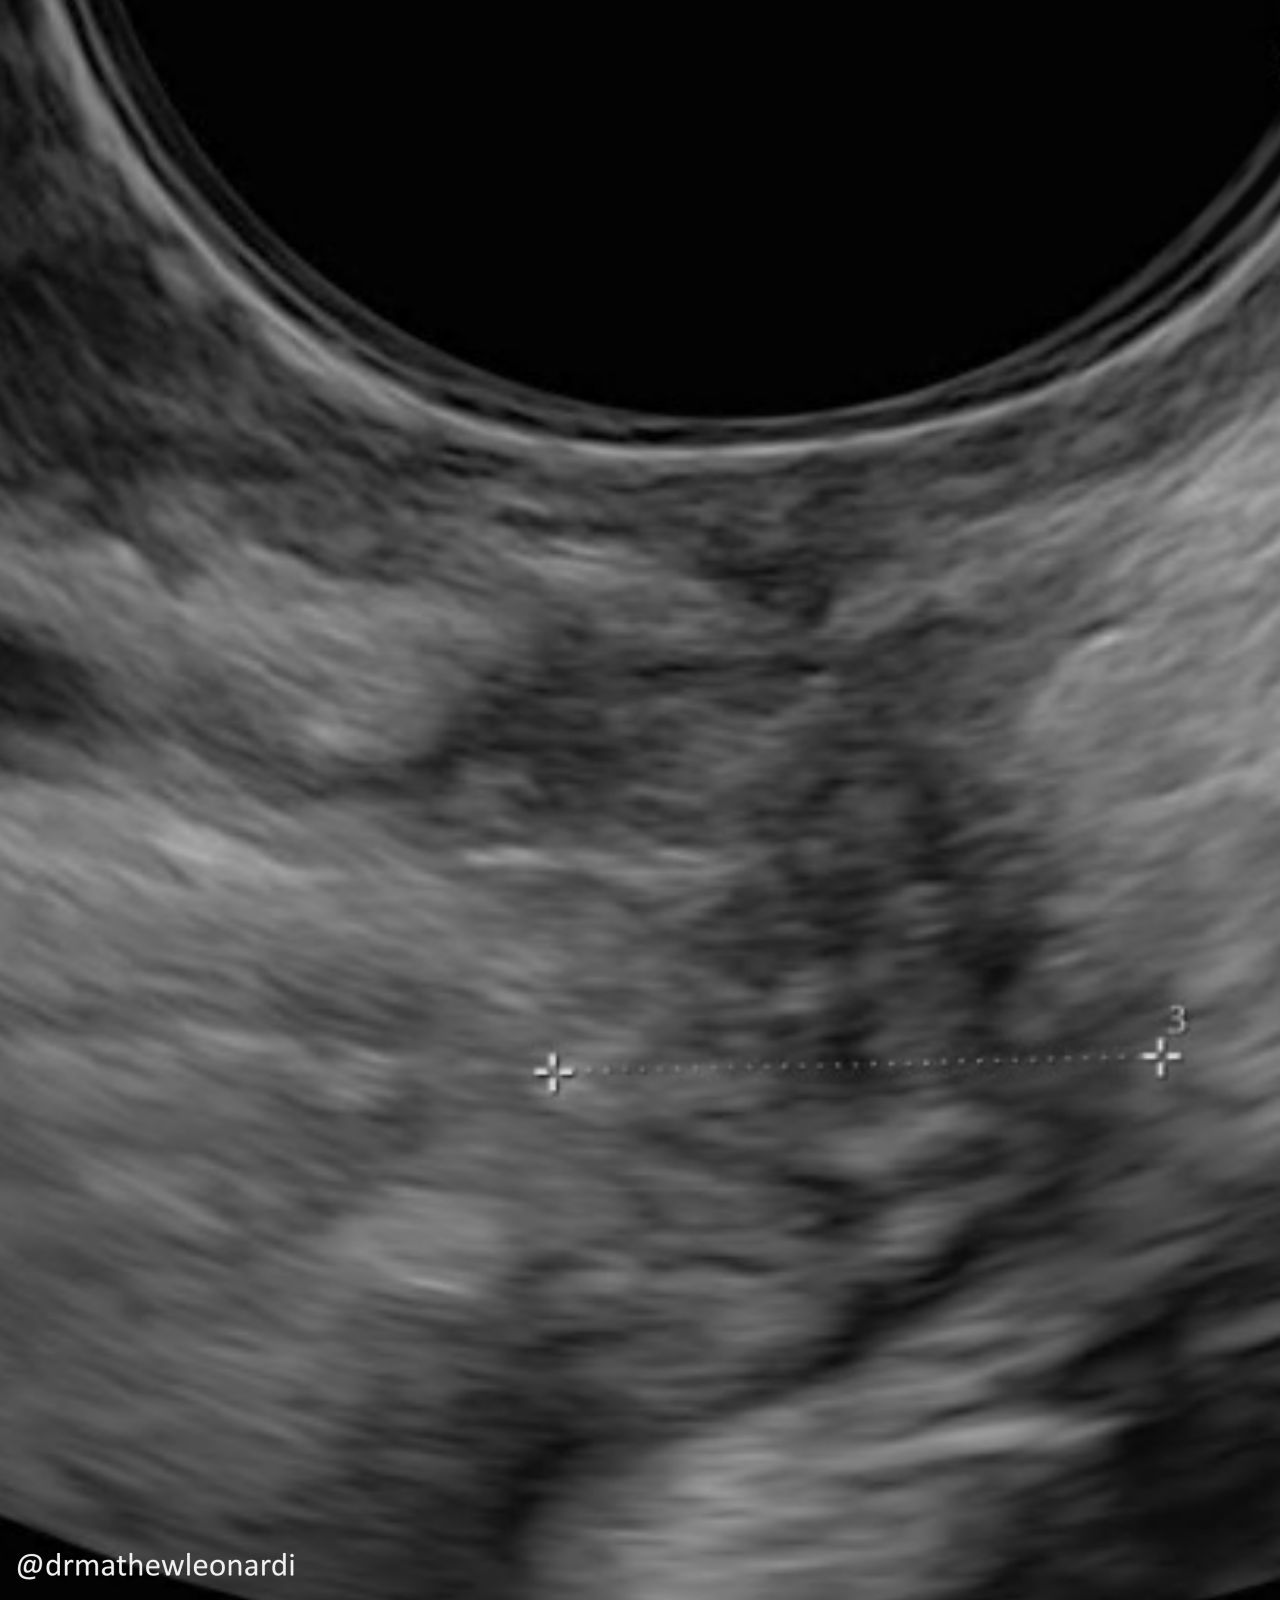

“Endometriosis does not have one single appearance, and that is part of why it is so often missed.

In this carousel, I’ve included a range of endometriosis lesions across different disease types and locations, including superficial disease, ovarian disease, and deep endometriosis involving areas such as the bowel, bladder, uterosacral ligaments, peritoneum, vagina, and ovary. A few are deliberately difficult because real-life recognition is not always straightforward.